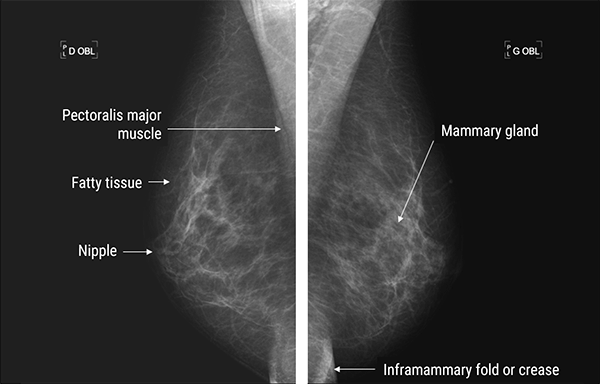

This mediolateral projection of the breast shows the petoralis major muscle, fatty tissue, the nipple and the inframammary fold or crease. Mammary glands are represented by the glandular tissue.